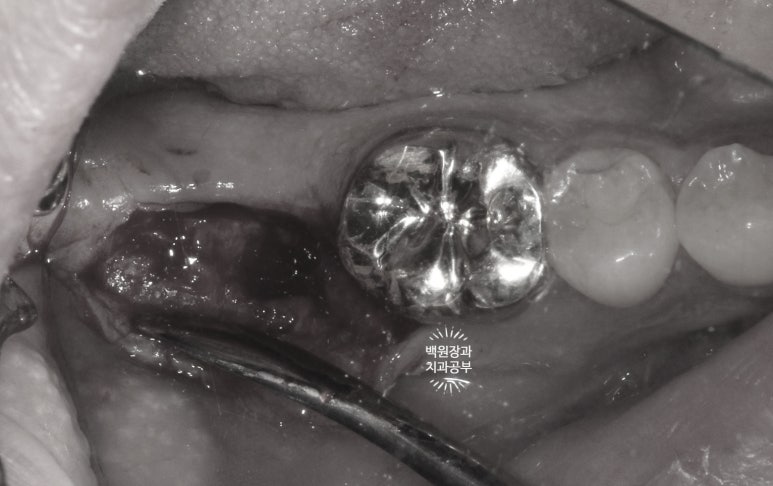

다시 한 번 간단한 시술을 통해 임플란트 주변 뼈이식이 잘 유지되고 있는지를 확인합니다.

덴티움 뼈이식재와 차폐막은 오랫동안 형태를 유지하며 조화로운 치료 결과를 보여주네요.

아주 만족스러운 결과를 직접 눈으로 확인하고 치유지대주 (Healing abutment)를 연결해드렸습니다.